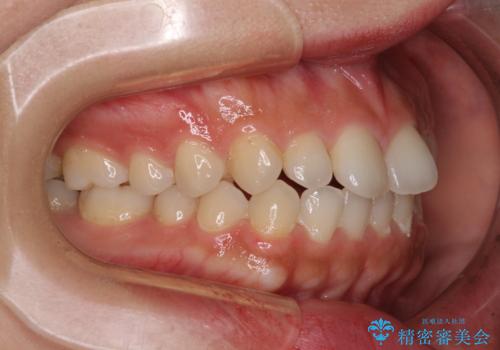

インビザラインを用いた上顎の部分矯正

- 上顎前歯の叢生を気にして来院された患者様です。

下顎前歯や上下奥歯の咬み合わせには殆ど問題がないため、上顎前歯のみを矯正する治療を提案しました。

ワイヤー装置でもインビザラインでも可能でしたが、前歯のみをきれいに排列するのであればインビザラインの方が仕上がりが良いので、インビザライン・ライトにて治療を行うこととしました。